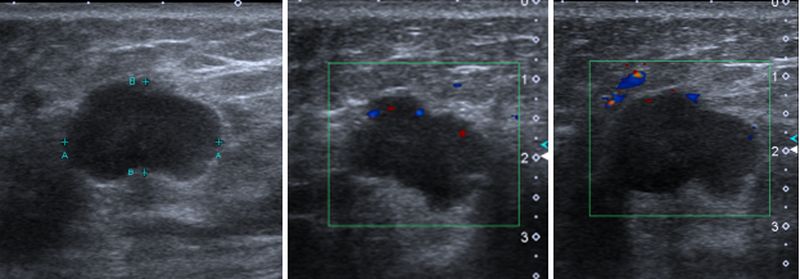

27歲上班族,無乳癌家族史。第一次做健康檢查,沒想到經乳房超音波檢查,在右乳外側發現一個20.7×12.2mm的低迴音腫塊,高度懷疑是惡性腫瘤,接受切片病理檢查證實為乳癌二期,已接受手術切除治療及化學治療。